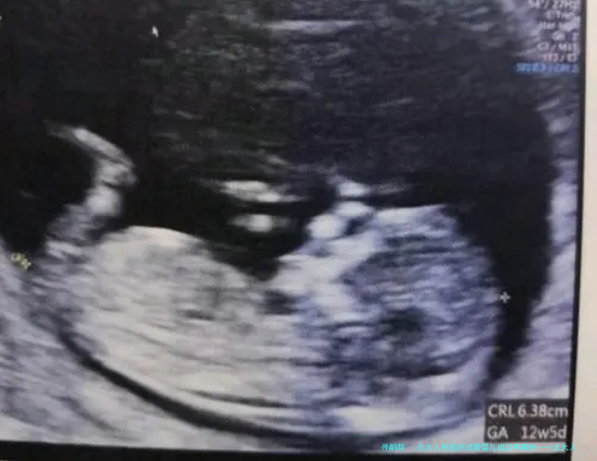

近些年来,随着我国人口老龄化问题的加剧,生育障碍问题也愈加突显。试管婴儿技术作为辅助生殖技术其中之一,为许多难育家庭带来了希望。北大人民医院作为国内闻名的三甲医院,在试管婴儿技术范畴具有丰富的经验和尖端技术。本文将从成功率的角度对北大人民医院试管婴儿技术进行剖析。

北大人民医院试管婴儿中心享有一支专业的医疗团队,采用国际先进的试管婴儿技术,为病人提供品质高的医疗服务。根据医院揭晓的数据,北小孩儿民医院试管婴儿成功率在业内处于领先水平。

北小孩儿民医院试管婴儿成功率受许多种因素影响,囊括病人岁数、不孕不育缘由、卵子质量、精子质量等。对在年轻时、卵巢机能优良的病人,成功率相应较高。此外,医院通过完善治疗方法、提高实验室技术水平等手段,不断提高试管婴儿成功率。